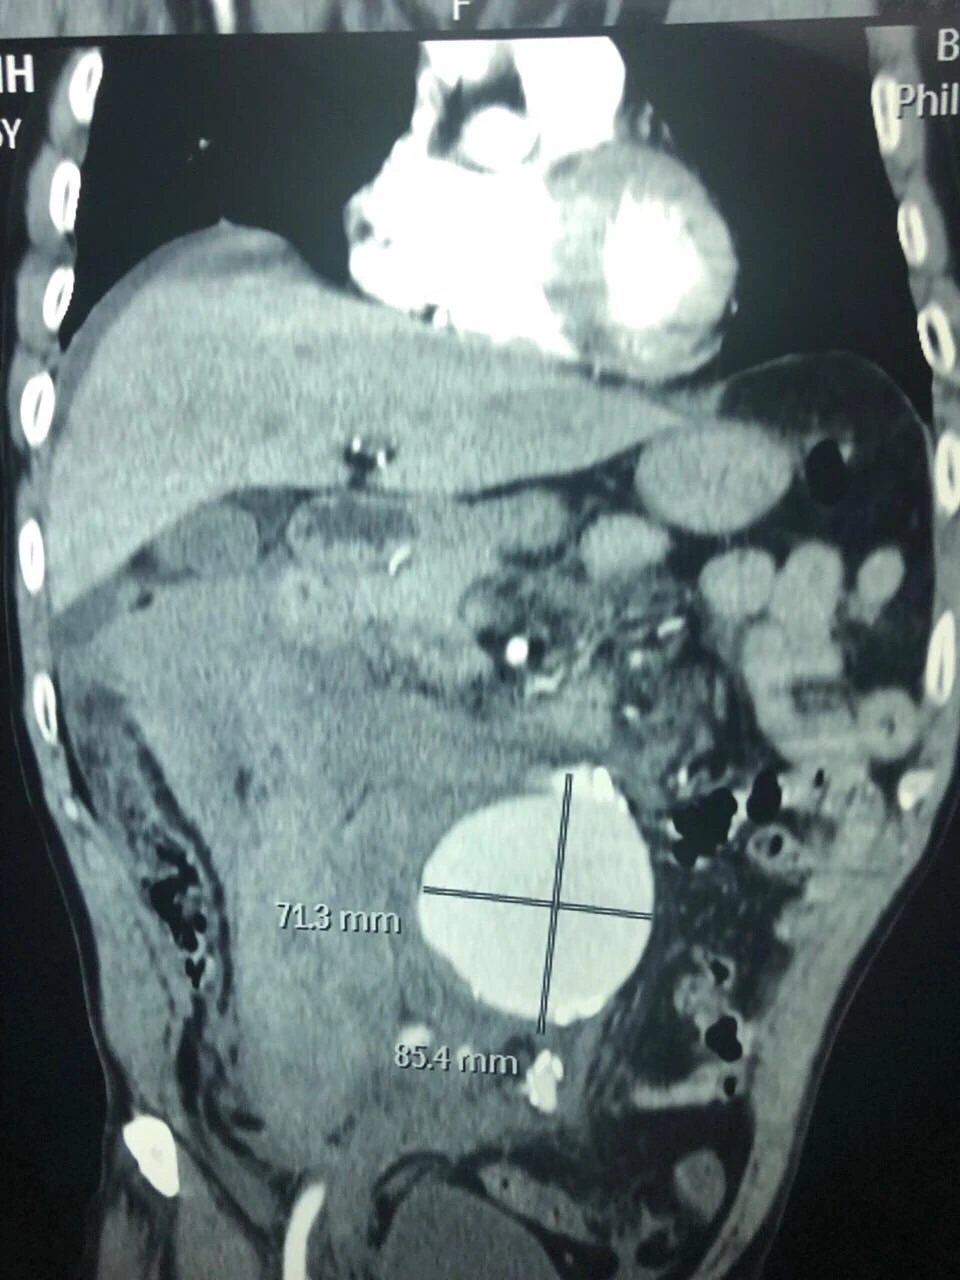

Túi phình động mạch chủ bụng của ông Đ. trên phim CT-scan. Ảnh: BVCC

Nhập cấp cứu tại BV Bình Dân trong tình trạng nguy kịch, sốc mất máu, tụt huyết áp, tri giác lơ mơ, tiếp xúc chậm, ông Đ. được các bác sĩ xác định vỡ túi phình động mạch chủ bụng đường kính 71mm. Sau đó ông được chuyển vào phòng mổ cấp cứu.